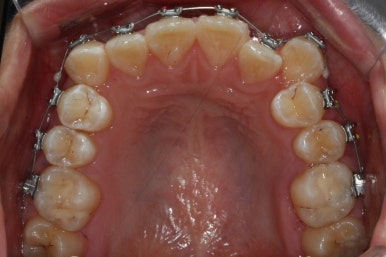

이제 가지런하게 하는 작업은 거의 종료되었고, 향후의 과정은 남은 이 뽑은 자리를 당겨주어 틈을 없애주면서도 입도 뒤로 좀 넣어주는 것이 되겠습니다.

위아래 아주 단단한 철사로 지탱해주면서 (앞니쪽에 고리가 달린 철사) 앞-뒤 치아를 서로 당겨주면서 이 뽑은 자리를 서서히 없애줍니다.

틈새를 모으는 작업을 반복적으로 행해주면 얼핏 봐서는 이뽑은 줄 모르게 치아가 서로 붙어있는 상황이 됩니다.

이제 이 뽑은 자리는 충분히 다 닫혔고, 틈새가 다시 벌어지지 않는지를 몇 개월에 걸쳐 확인한 뒤 그동안 디테일한 마무리 과정을 해주게 됩니다.